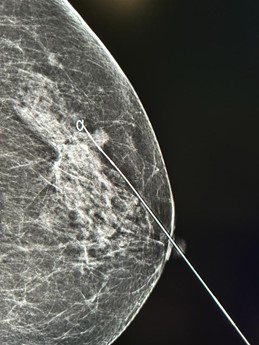

Sharing some photos from our European partner: Curaway's Q-version wire under imaging.

Wire localization is very helpful for small and nonpalpable tumors in breast, which helps to remove the tumor completely, while preserving the normal breast tissue.

Curaway's Q-version wire is CE and FDA approved, it is made of nitinol with good biocompatibility, available for repeatable positioning and anchoring the lesion firmly.